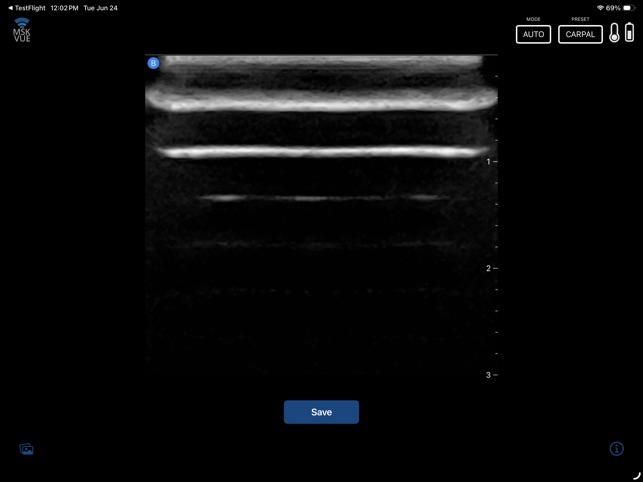

MSK VUE is a specialized training application for musculoskeletal ultrasound. The system utilizes an artificial intelligence component to support the identification of key peripheral anatomical structures within an interactive, simulated ultrasound imaging environment. The interface is designed to present visualizations of nerves, tendons, and bones, allowing users to engage with the simulated data. This application's core mechanism focuses on presenting specific anatomical targets and facilitating their recognition through its AI-driven framework, providing a platform for practice in a non-clinical context.

This application is designed for clinicians seeking to develop proficiency in musculoskeletal ultrasound. It functions as a supplementary educational tool for practicing the identification of peripheral anatomical structures within a simulated environment. This app is intended for educational purposes and does not replace professional medical advice, diagnosis, or treatment; the provided description explicitly prohibits its use in any clinical setting or for any clinical purposes.